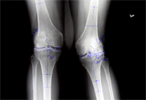

54 years old female with rheummatoid arthritis and valgus deformity right knee

Pre

Op

Pre Operation Xrays of limb